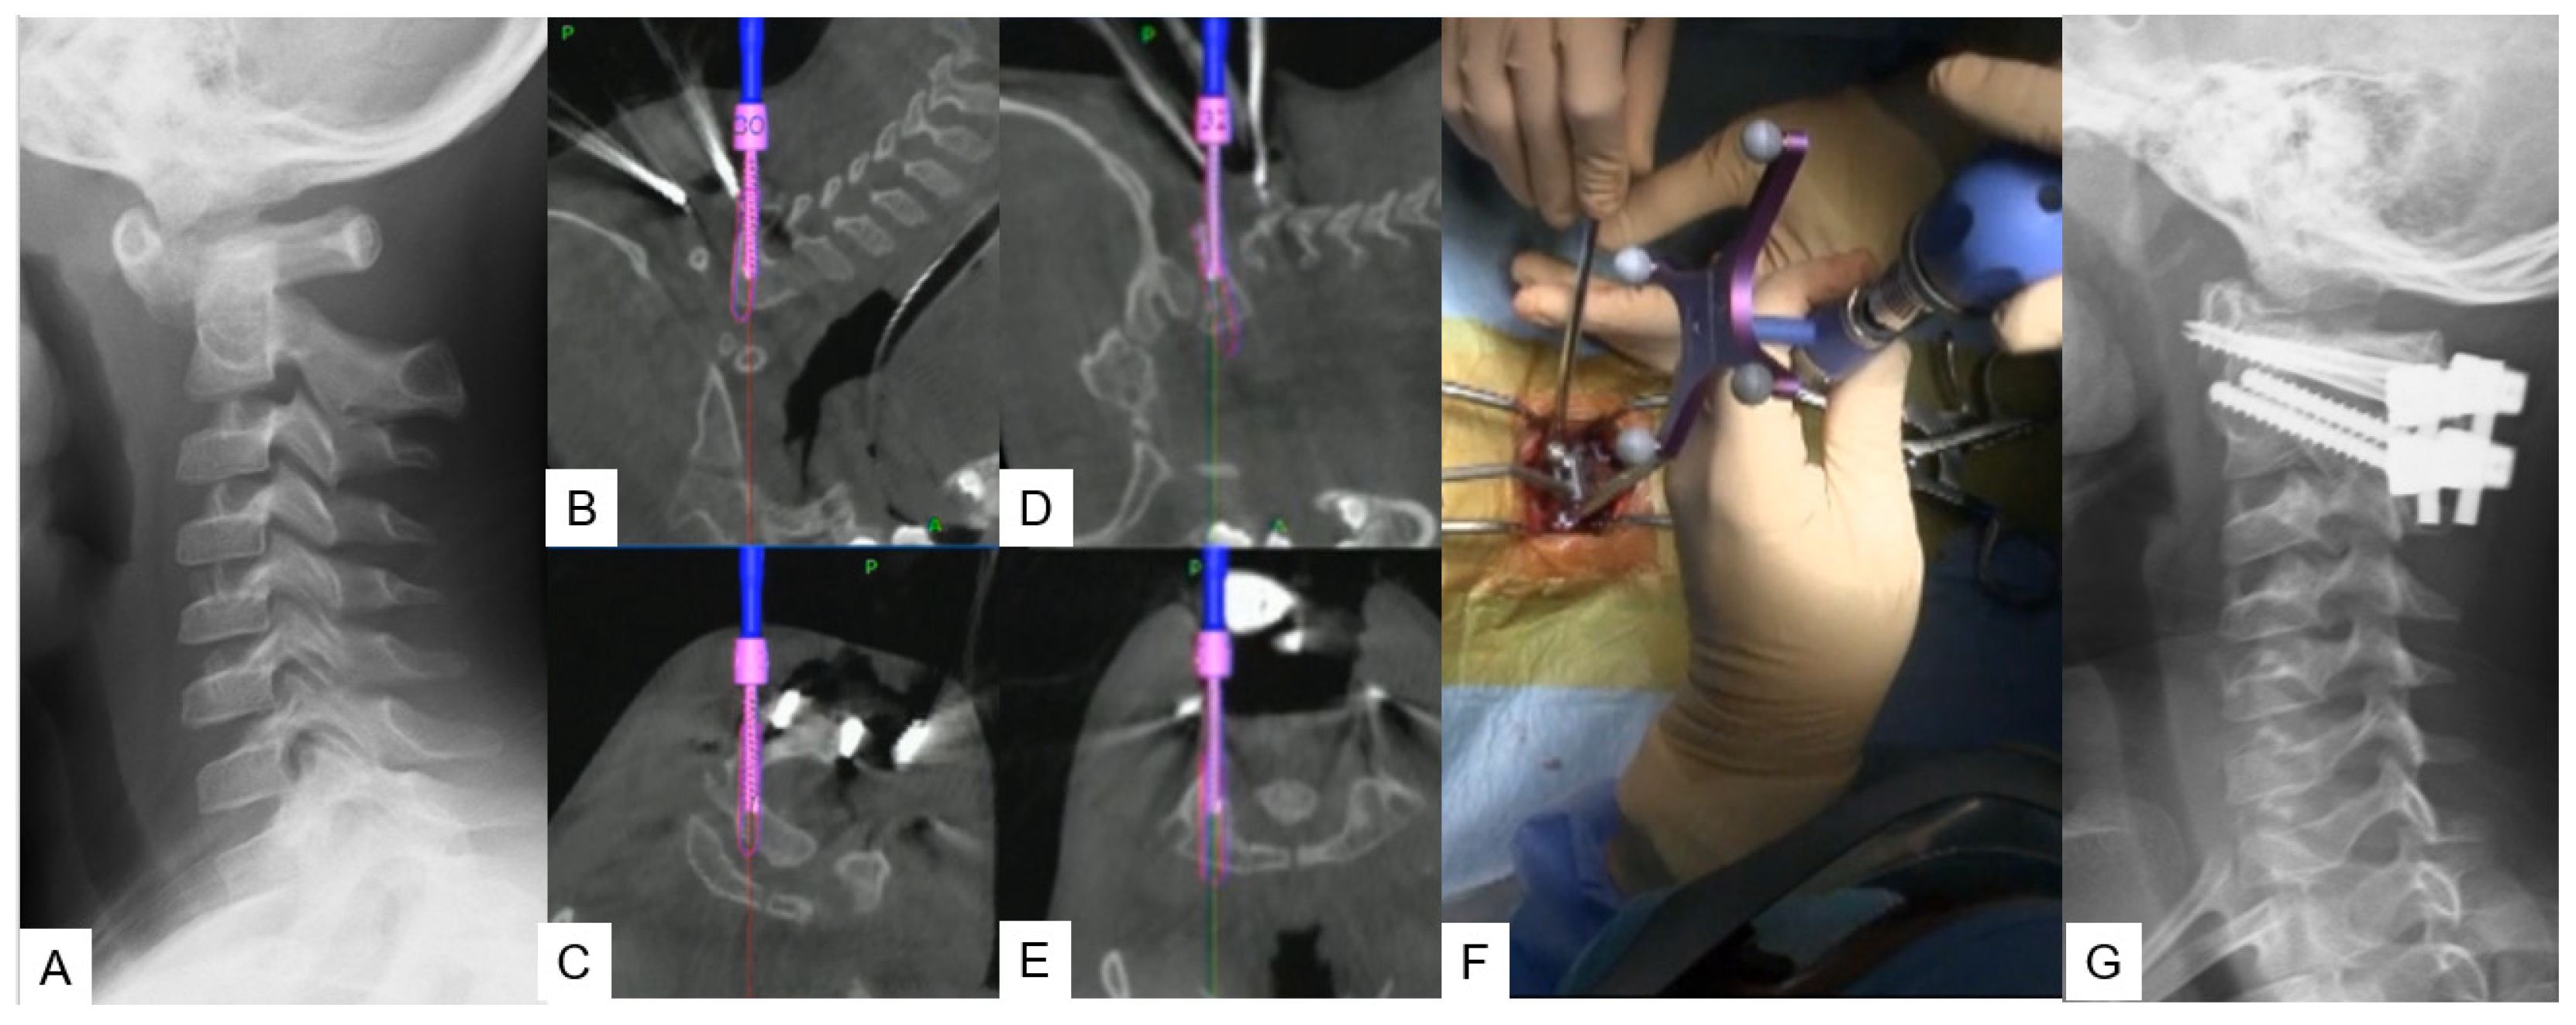

2.2.2. Modified Goel Technique

- Tanaka, M.; Sonawane, S.; Fujiwara, Y.; Uotani, K.; Arataki, S.; Yamauchi, T.; Ye, Y.; Misawa, H. C-arm Free O-arm Navigated Posterior Atlantoaxial Fixation in Down Syndrome: A Technical Note. Acta Med. Okayama 2022, 76, 71–78. [Google Scholar]